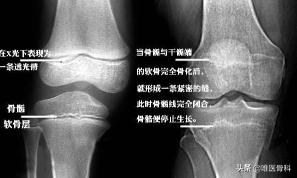

什么是骨骺线?骨骺线就是骨骺与干骺端之间的软骨,在X光片上表现为一条较宽的透光带,它随着年龄的增长而逐渐变短。